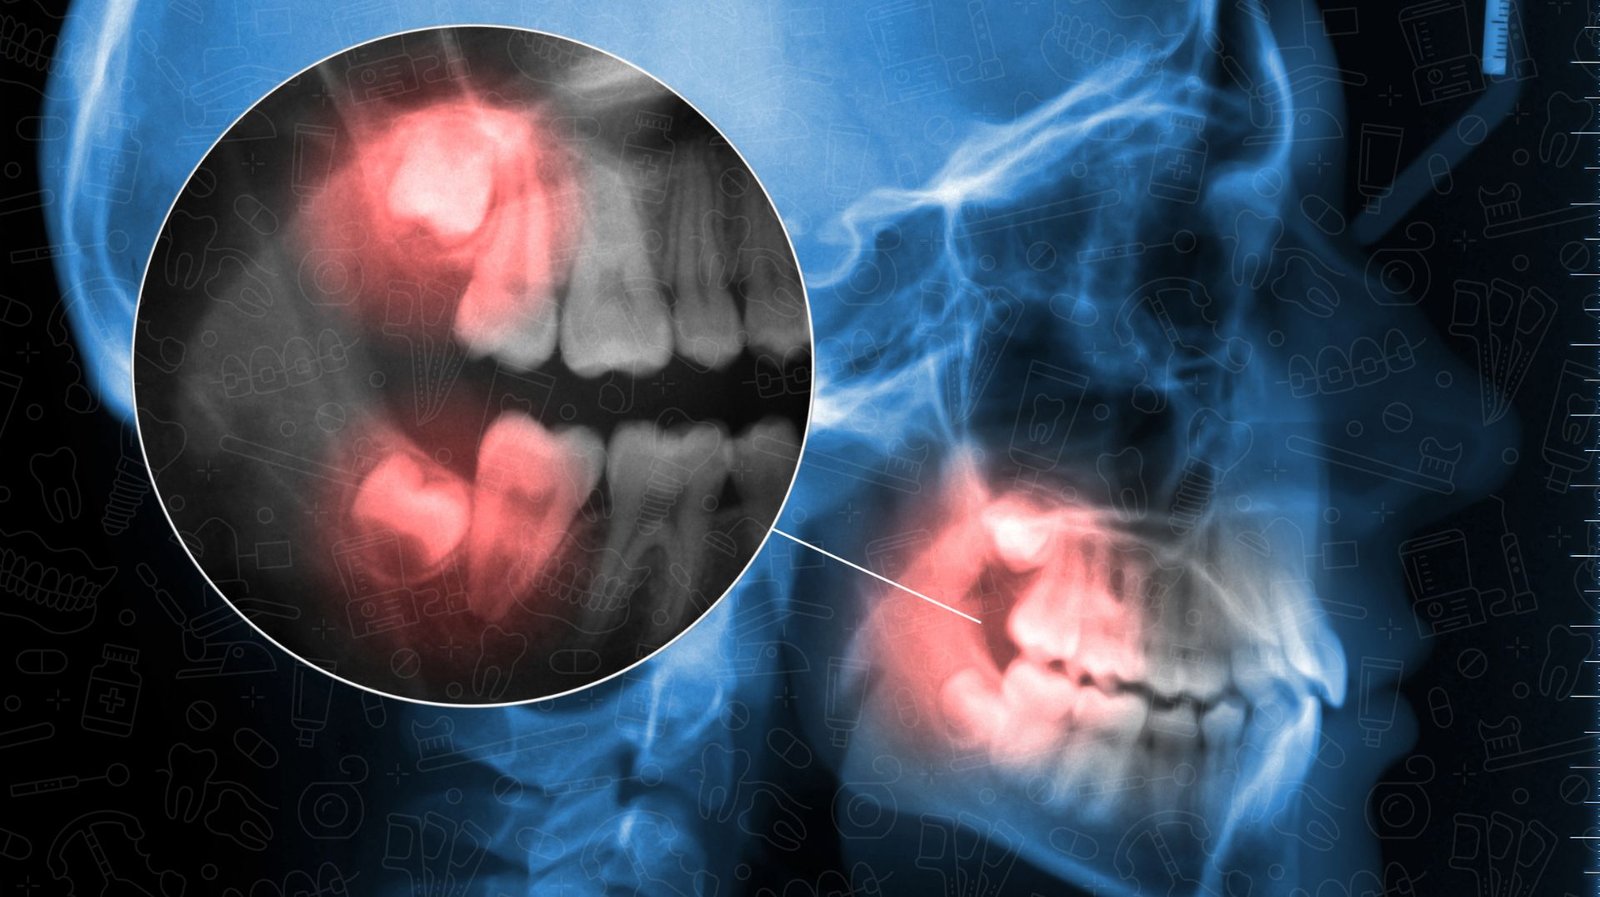

Wisdom tooth removal is a common dental procedure aimed at extracting third molars, often referred to as wisdom teeth. These teeth typically emerge in late adolescence or early adulthood, usually between the ages of 17 to 25. Due to limited jaw space, wisdom teeth may become impacted, leading to complications such as infections, overcrowding, or misalignment of adjacent teeth.

Dentists often recommend this extraction as a preventive measure to avoid future dental issues. In many cases, the removal is performed on an outpatient basis under local or general anesthesia, ensuring patient comfort. Typical dental evaluations, including X-rays, help determine the positioning of these teeth and any potential impact on oral health.

During the visit, X-rays will likely be taken to assess the positioning of the wisdom teeth and identify potential complications. These images allow the dental professional to formulate a tailored surgical plan. Additionally, patients should disclose their complete medical history, including any medications they are taking, to avoid adverse reactions during the procedure.

Once the anesthesia takes effect, the dentist or oral surgeon will begin by carefully assessing the position of the wisdom tooth using X-rays. This imaging assists in determining the most effective extraction technique. If the tooth is fully erupted, it may be removed similarly to a standard tooth extraction. However, if the tooth is impacted, the surgeon may need to make a small incision in the gum and, if necessary, remove bone tissue obstructing the tooth.